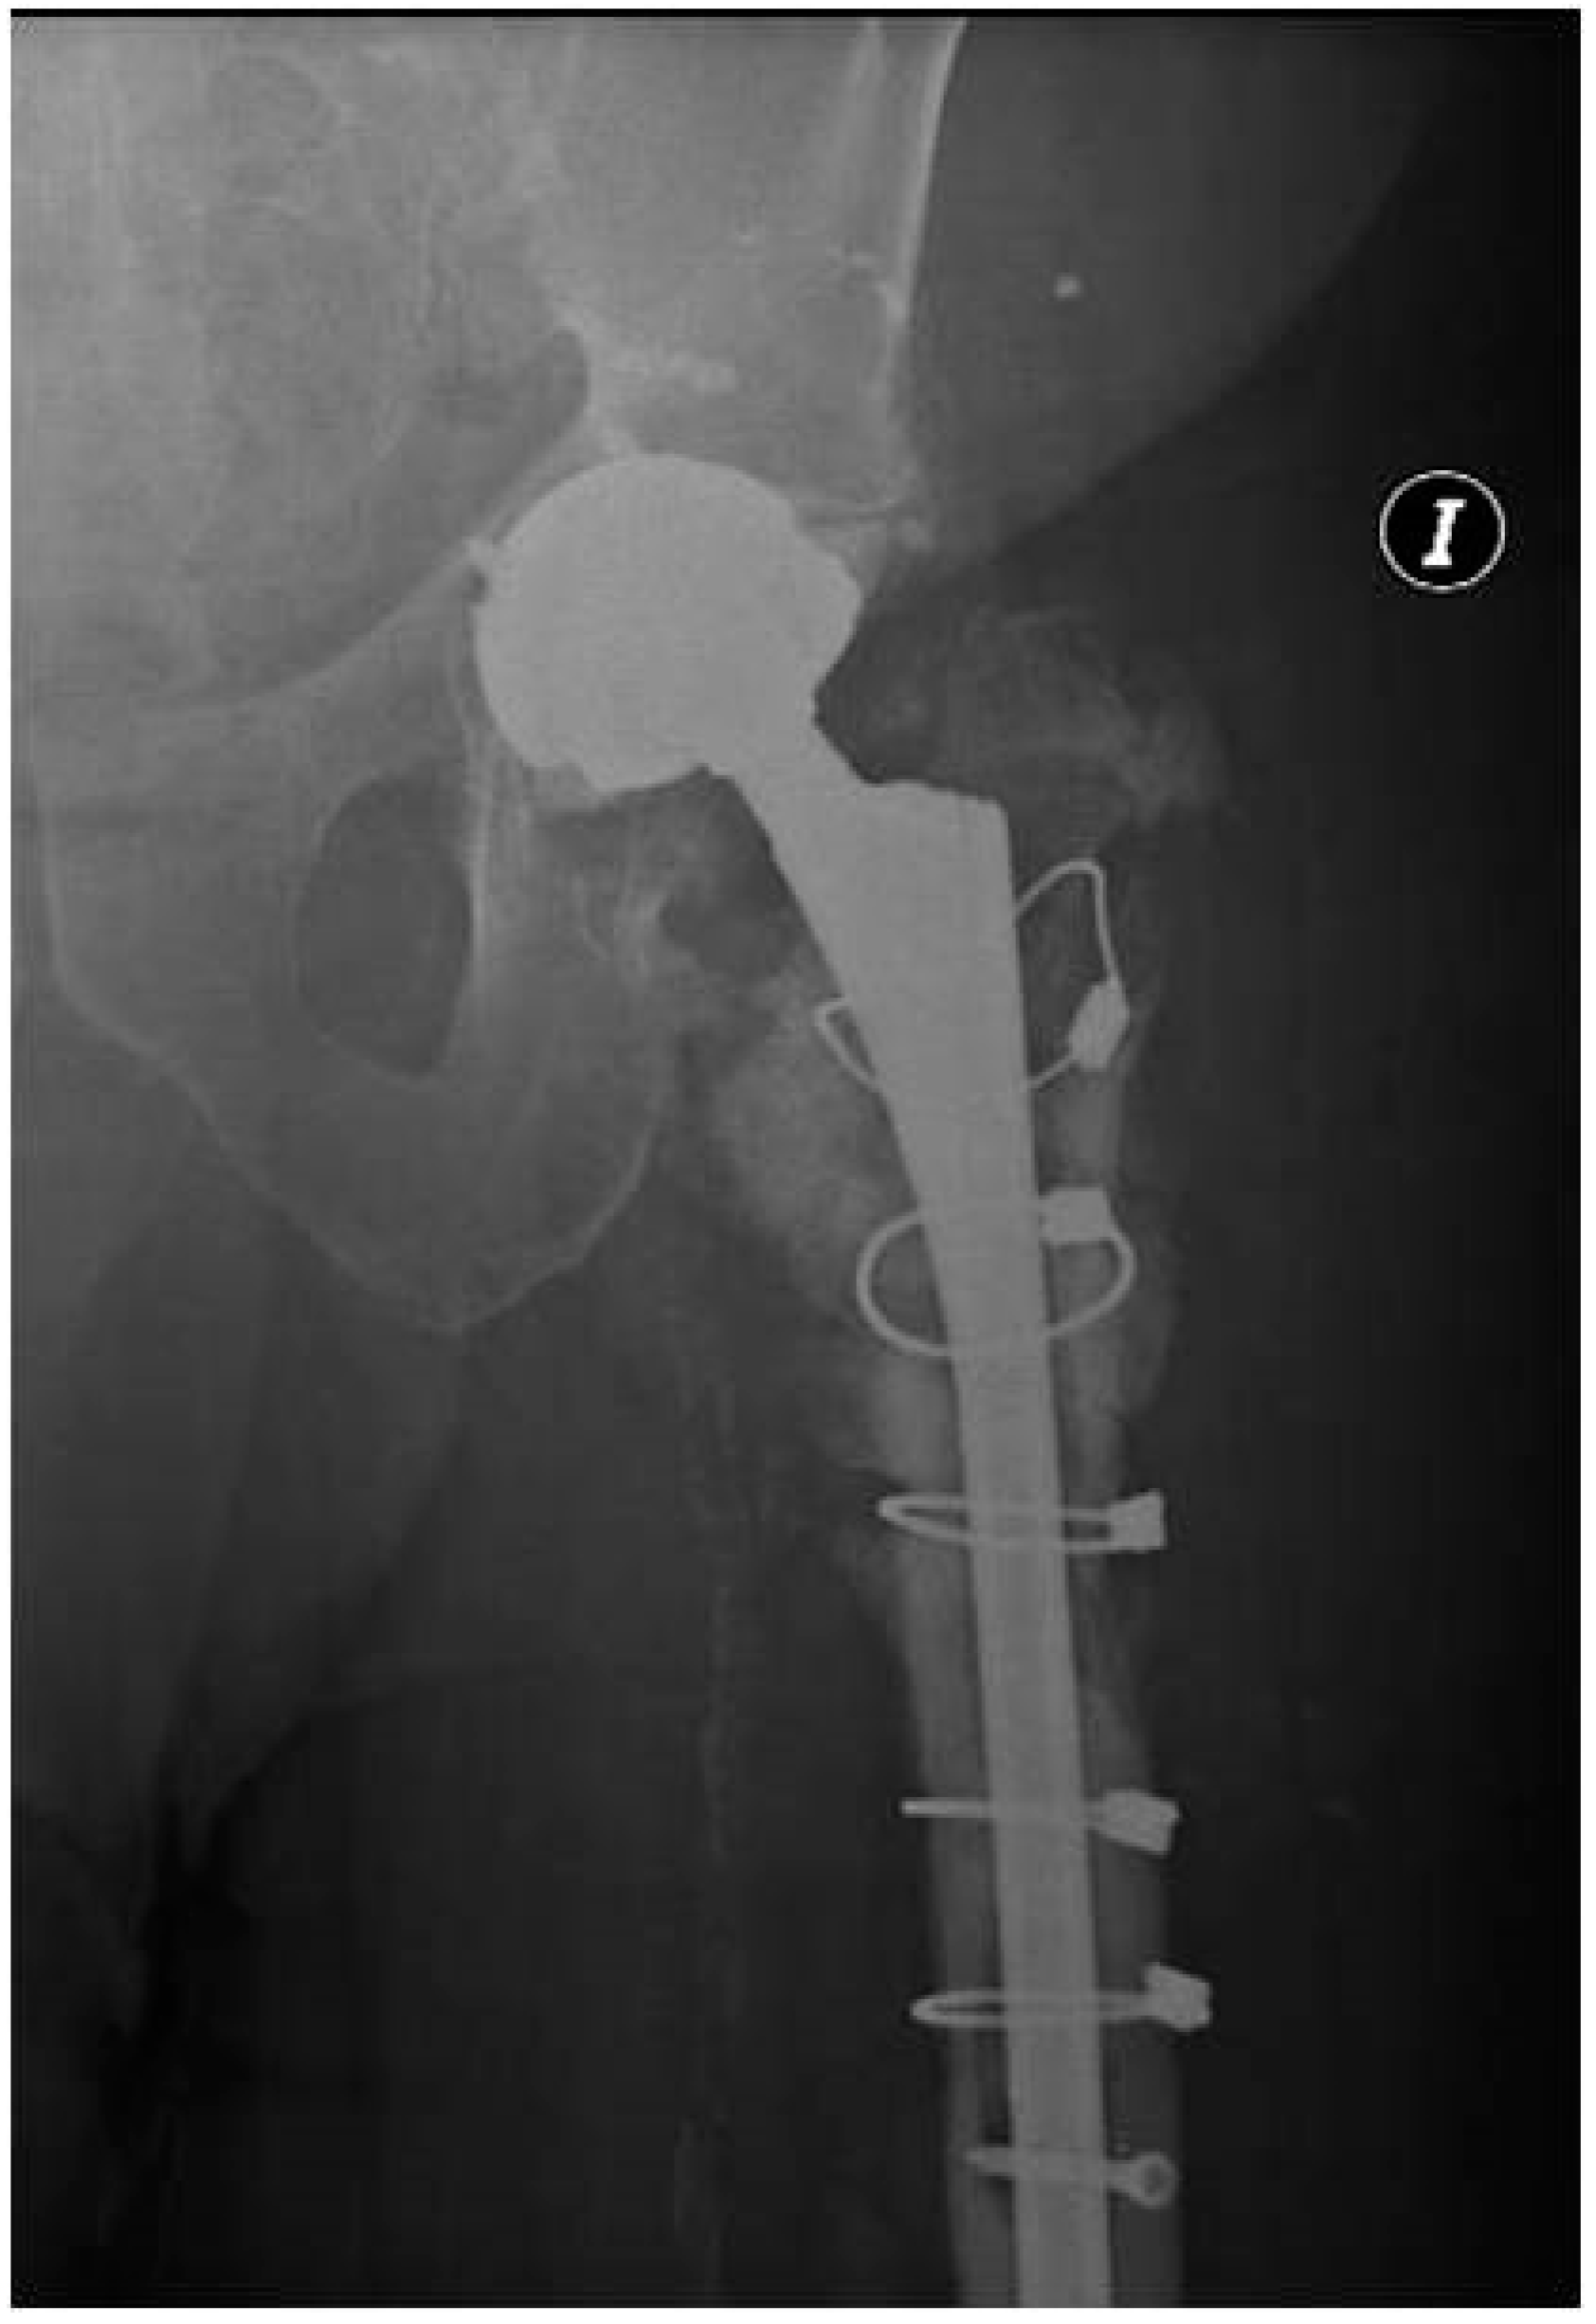

2.2. Case 2